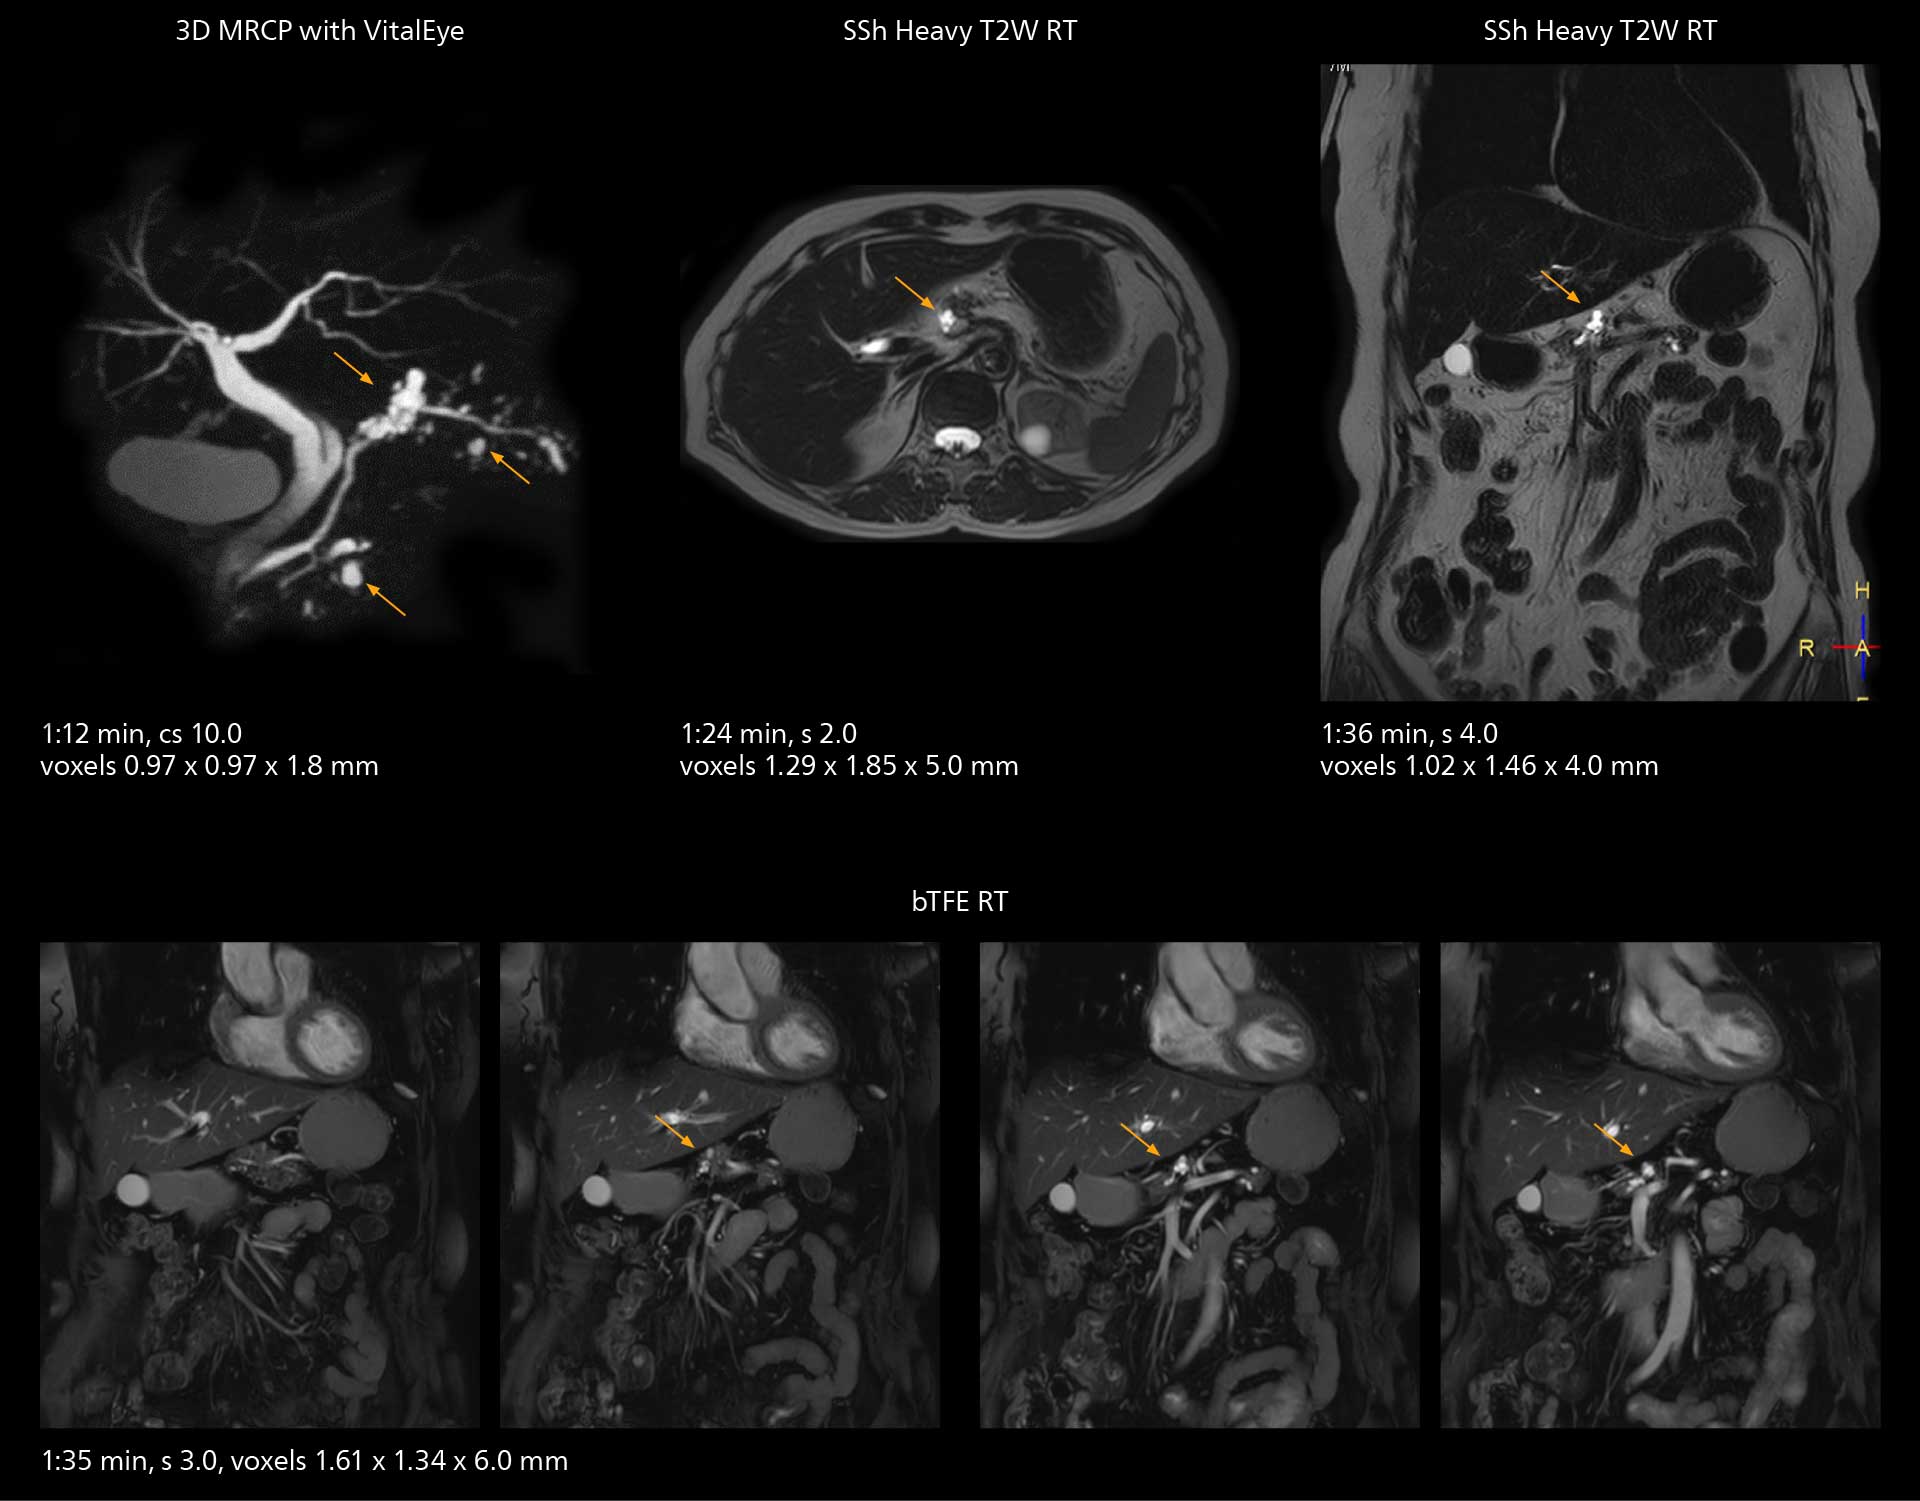

SmartPath to Elition X comes with Smart Workflow technologies that support technologists and can save them time. VitalEye for touchless patient sensing is one example. “The implementation of VitalEye respiratory synchronization has had a significant impact,” says MR technologist Yoshihiro Otsu, Chief of the Radiological Department. “It not only improves workflow, but it also has increased the quality of examinations. Particularly for the large number of MRCP examinations performed in this hospital, VitalEye has increased the possibility to obtain sharp images with less blurring. Clinicians here really appreciate this improvement in MRCP image quality.” The VitalScreen on the scanner has helped reduce the risk of patient misidentification. “It allows patient information to be viewed in the magnet room when standing next to the patient,” he says. “And the automated patient centering in the magnet is very useful as well.” Apart from reducing stress for technologists, Smart Workflow helps improve respiratory synchronization and reduce examination stress for the patient.

With SmartPath to Elition X, the MRCP examinations at Sannodai Hospital benefit from VitalEye: respiratory synchronization is possible without respiratory belt positioning and image quality is excellent.